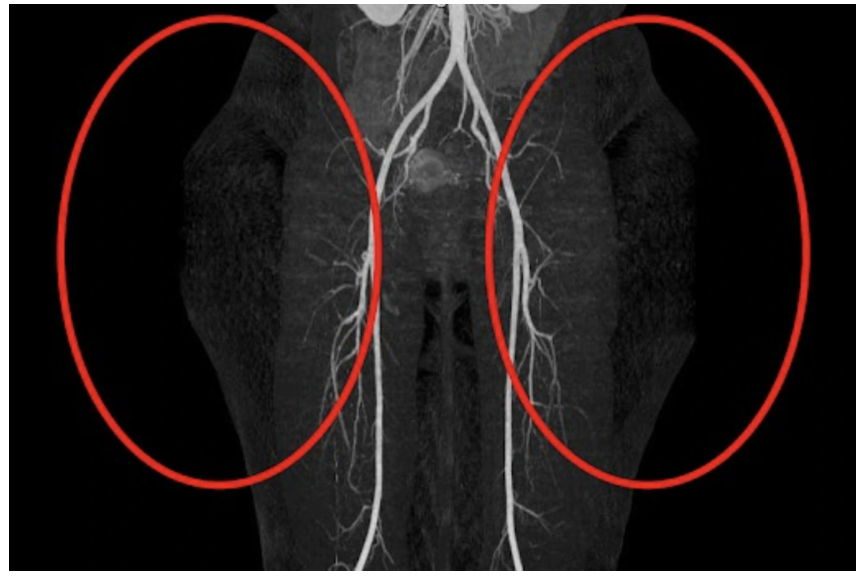

Dựa trên hình ảnh siêu âm màu và kết quả chụp CT mạch máu chi dưới, các bác sĩ bệnh viện tại TPHCM chẩn đoán bệnh nhân mắc phải hội chứng Madelung vùng mông, một bệnh lý cực kỳ hiếm làm mỡ phát triển bất thường, đối xứng hai bên vùng mông và hông.

Kết quả chẩn đoán hình ảnh cho thấy, khối mô mỡ của bệnh nhân có độ dày lên đến 8.2cm mỗi bên, với tổng chu vi vùng hông 138cm, vượt xa tiêu chuẩn bệnh lý thường gặp trong thực hành lâm sàng.

Sau ca phẫu thuật kéo dài 6 giờ, các bác sĩ đã bóc tách mô mỡ lan tỏa, bảo tồn cấu trúc mạch máu, thần kinh, đồng thời tái tạo thẩm mỹ vùng mông, hông và đùi cho bệnh nhân.